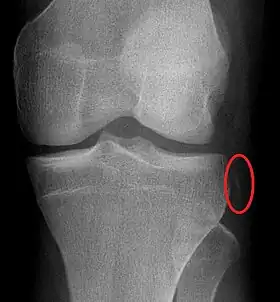

La fracture de Segond est une fracture par avulsion. Elle affecte le condyle du tibia, à proximité immédiate du plateau tibial, au point d’insertion du ligament antéro-latéral (formation antéro-externe FAE).

À la radiographie de face[6], la fracture de Segond présente une pastille d’os d’une taille caractéristique (voir l'image). Mais ce fragment peut être très difficile à discerner aux rayons X, et il s'observe mieux par tomographie numérique. Quant à l’imagerie par résonance magnétique (IRM), elle permet de mettre en évidence l’œdème associé du plateau tibial, ainsi que les lésions ligamenteuses ou méniscales également associées.